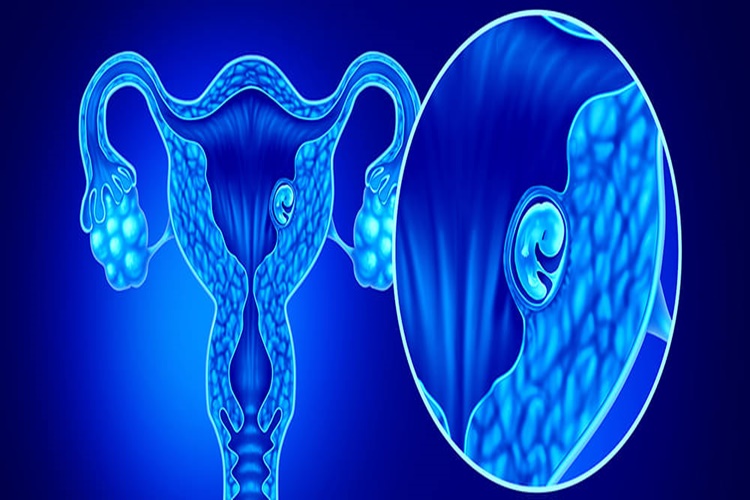

Burun polipleri tedavi edilebilir bir rahatsızlıktır ve başlarda tehlikeli olarak belirtilmez. Ancak tedavi edilmeyen burun polipleri zaman içinde tehlike arz eder. Burun polipleri burunda kanser oluşumuna neden olabilir. Burunda oluşan tümörler kontrol alınmadığında ise tümör diğer dokulara yayılır ve lenf ya da kan dolaşımı üzerinde tehlike oluşturmaya başlar.